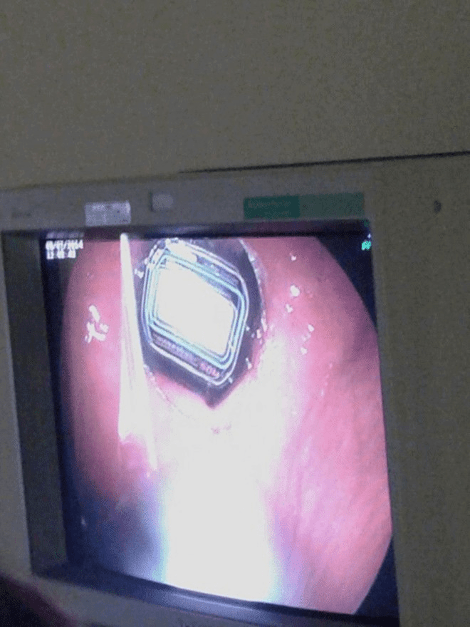

Χειρουργοί αφαίρεσαν από το στομάχι ασθενή ένα ρολόι.

Η επέμβαση που διήρκεσε περίπου τρεις ώρες, πραγματοποιήθηκε στο Πανεπιστημιακό Νοσοκομείο Ηρακλείου, όταν κρατούμενος των φυλακών της Νέας Αλικαρνασσού μεταφέρθηκε άρον άρον με πόνους στο στομάχι.

Πάντως, δεν είναι η πρώτη φορά που οι γιατροί έρχονται αντιμέτωποι με τέτοια περιστατικά, καθώς έχουν αφαιρέσει από το στομάχι κρατουμένων μέχρι και νυχοκόπτη, ενώ οι πλύσεις στομάχου λόγω κατάποσης απορρυπαντικών είναι πολύ συχνό φαινόμενο.